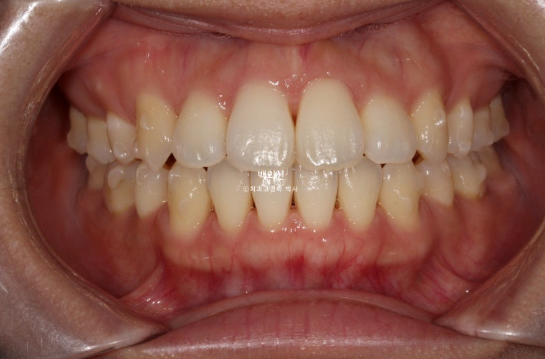

드디어 80개 장치를 다 낀 것은 24년 8월입니다. 치료시작 1년 8개월째입니다.

24.08

중심선은 잘 맞고 앞니 교합도 좋습니다.

발치공간은 다 닫힌 것 처럼 보이지만 치실이 헐렁하게 들어가는 정도의 미세공간은 남아있습니다.

미진한 부분들을 개선하기 위해서 추가장치 재제작에 들어갔고 24년 9월부터 25년 4월까지, 25개의 추가장치를 다 낀 후 모습입니다.

25.04

모든 게 좋지만 환자분의 요구사항은 왼쪽 앞니 하나가 기울어져 것이었습니다.

이 부분을 해결하고자 추가장치를 한 번 더 쓰기로 합니다. 25년 5월부터 7월까지 10개의 추가장치를 더 낀 후 드디어 치료를 마무리 했습니다.